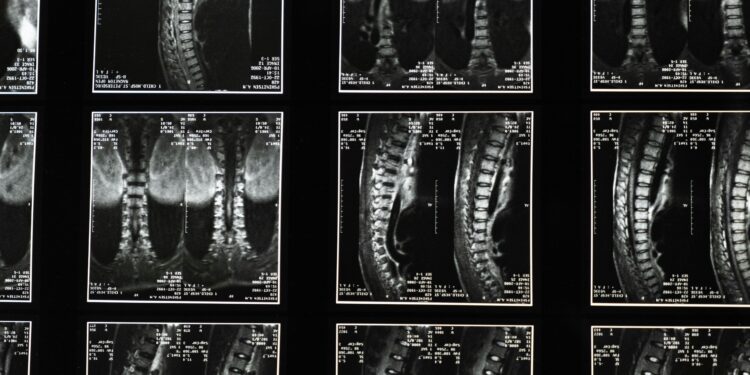

Medical Imaging and Specialist Evaluation: Why They Matter

Back and spine injuries aren’t always visible immediately. X-rays can miss disc injuries and soft tissue damage. MRIs often provide the clearest picture of disc herniations, nerve compression, and spinal cord issues. CT scans may be critical for fractures.

Specialist evaluation—neurology, orthopedics, neurosurgery—can also strengthen the clarity of diagnosis and treatment needs. Insurance companies often respect specialist documentation more than vague notes from early urgent care visits.